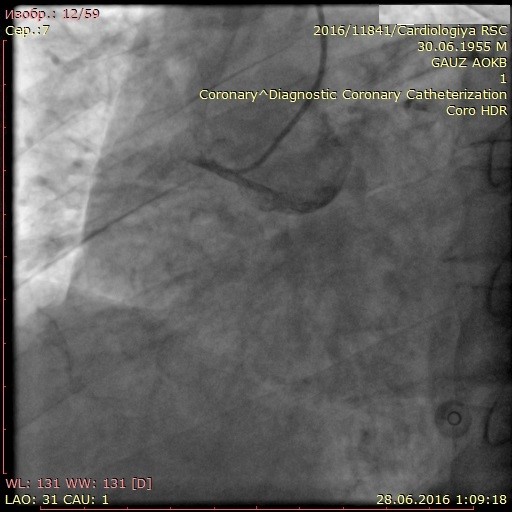

Цель исследования: Оценить перфузию и функцию миокарда при развитии окклюзии коронарной артерии и различных вариантах коллатерального кровообращения.

Материал и методы: 90 пациентов с трехсосудистым поражением коронарного русла и обязательным наличием окклюзии правой коронарной артерии (ПКА) в зависимости от варианта развития коллатерального крвоснабжения были разделены на две группы: в первую группу вошли 44 пациента (44%) с наличем коллатералей I и II степени градации по Rentrop, во вторую группу – 46 пациентов (56%) с наличием коллатералей 3 градации по Rentrop. Проанализированы данные перфузионной сцинтиграфии, эхокардиографии и тканевой допплерографии.

Результаты: Выявлено ухудшение перфузии миокарда по нижней стенке у пациента из второй группы при незначимом дефекте перфузии у пациента из первой группы. СДП в 1 группе составил 9,8±3,5%, во второй группе – 4,1±1,7%. При сравнении показателей тканевой допплерографии более значимое изменение продольной деформации в области нижней стенки левого желудочка выявлено в группе с плохим коллатеральным руслом: – 4,1±2,6, во 2 группе: – 6,8±2,7. При оценке сегментарной сократимости нижней стенки левого желудочка выявлено меньшее количество сегментов гипокинеза в группе 2.

Заключение: Хроническая окклюзия коронарной артерии со слабым коллатеральным кровоснабжением сопровождается худшими показателями локальных перфузии и функции миокарда. При хорошем развитии коллатералей, несмотря на незначимые нарушения перфузии миокарда в покое, имеются отчетливые стресс-дефекты перфузии и нарушения локальной сократимости миокарда.